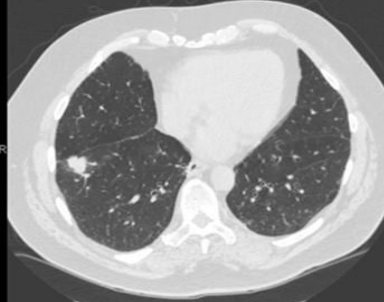

An 80-year-old man with past medical history of Hypertension and type-2 diabetes mellitus. He presented to his primary care physician for change of his urine color which he described as tea colored and he passed three very small stones. The primary care physician ordered a non-contrast CT abdomen with renal protocol to evaluate for renal calculus. The CT abdomen showed no renal calculus but it picked up a 23 mm right lower lobe pulmonary nodule (Figure1). The patient was referred to positron emission tomography scan (PET scan). The PET scan showed hypermetabolic activity in the right lower lobe nodule.  the nodule had standardized uptake values (SUV) 10.7. This was highly suspicious for malignant etiology of the lung nodule. There was no other significant finding on the PET scan to suggest malignancy anywhere else but the lung nodule. There were no significant hypermetabolic activities of the mediastinal and hilar lymph node.  The patient was referred to our interventional pulmonary clinic. The patient has chronic dry cough without hemoptysis. He denies any shortness of breath or dyspnea on exertion. He denies any history of smoking or significant history of occupational exposure. We discussed with the patient performing bronchoscopy and biopsy and he agreed on the procedure. A robotic bronchoscopy was performed and transbronchial lung needle aspiration TBNA with 21 gage needle and transbronchial lung biopsies with 2 mm forceps were obtained from the lung nodule. Endobronchial ultrasound with TBNA from mediastinal and hilar lymph nodes were obtained.  All TBNS and biopsies were sent for cytology and pathology.  Lung nodule pathology showed diffuse large B-Cell lymphoma (DLBCL). Lymph node TBNA showed normal lymphocytes. DLBCL was limited to the lung nodule only.

Figure 1: Right lower lobe lung nodule.